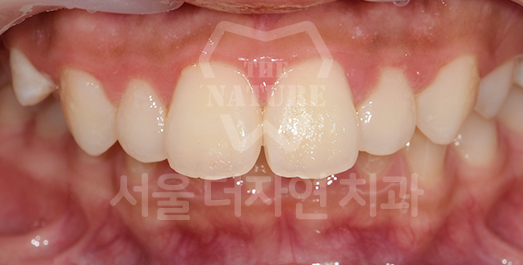

벌어진 치아교정 Solution

치아 벌어짐이 전체적으로 있는지 또는

부분(앞니 등)에만 있는지를 진단하고,

교정 장치를 부착하고 빈 공간으로

치아를 이동시켜 맞춰주는 방법으로 치료합니다.

BEFORE: 2020.11.12

-

AFTER: 2023.04.06